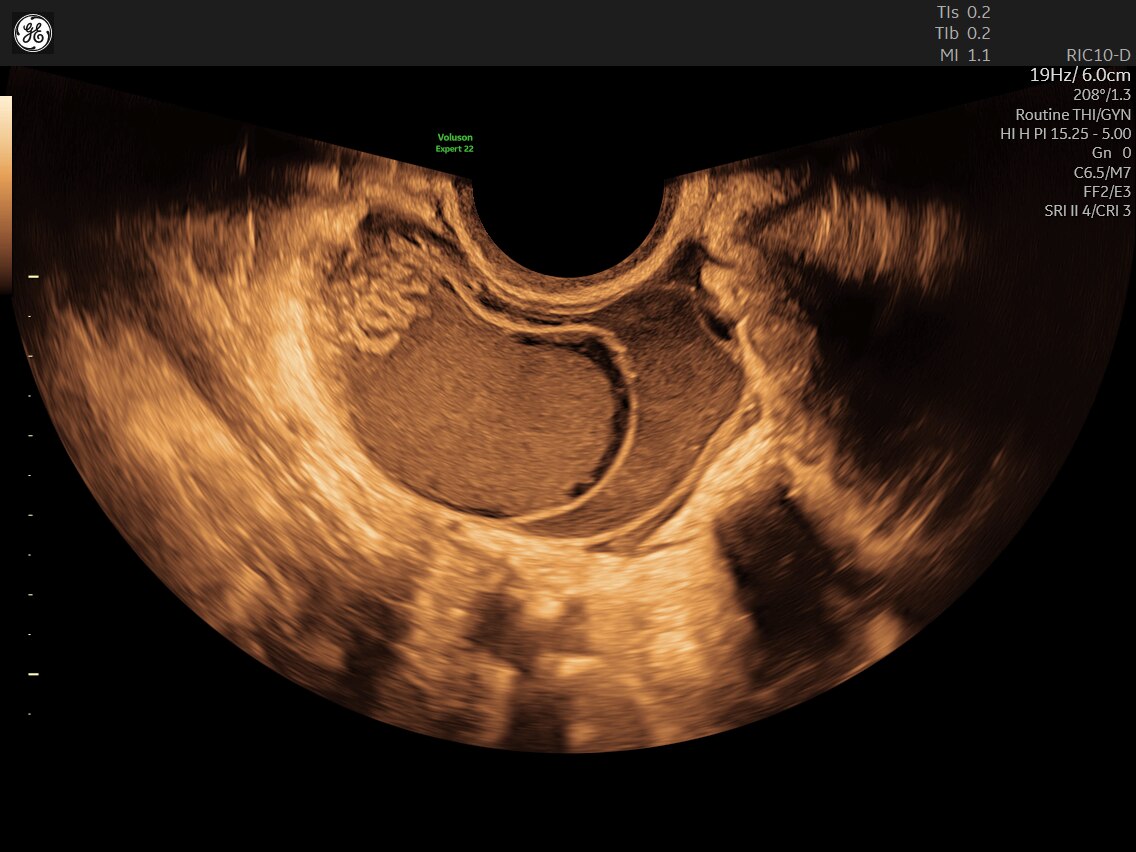

Discover complicated anomalies and pathologies with the Voluson Expert 22 to provide answers sooner for better decision making.

Complex cases come with enough uncertainty. That's why the Voluson Expert 22 is specifically designed for in-depth assessment of complicated anatomy — with pioneering first trimester, fetal cardiac, gynecological, and other pivotal technologies that focus on early detection and intervention.

Identifying fetal cardiac abnormalities earlier means you can intervene sooner, plan for delivery, and potentially improve outcomes. The Voluson Expert 22 provides a full solution of progressive tools, to help distinguish the tiniest structures with stunning clarity to provide patient answers faster.